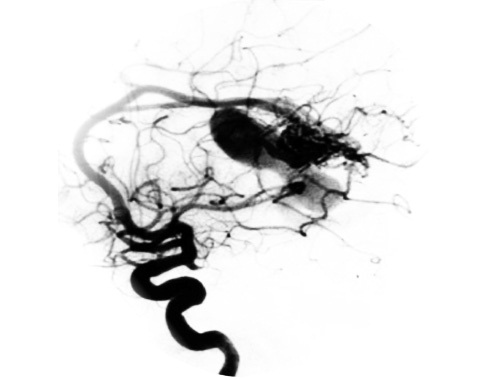

Se trata de un tratamiento que sirve para ocluir de forma parcial o total las malformaciones arteriovenosas cerebrales mediante su taponamiento realizado desde el interior de su arteria y guiado con rayos X (tratamiento endovascular).

Se realiza para evitar su ruptura o para evitar un nuevo sangrado cuando la malformación ya ha debutado con una hemorragia cerebral. En ciertos casos será posible conseguir el cierre total de la malformación en una o en varias sesiones de embolización. Otras veces, cuando la malformación es muy grande, la embolización se realiza para facilitar la cirugía o reducir su tamaño antes de la radiocirugía.

Se pincha un vaso sanguíneo, generalmente de la ingle y a continuación se introducen en su interior unos tubos flexibles, llamados catéteres, que llegarán hasta los vasos sanguíneos del cuello. A través ellos, se introduce otro pequeño catéter que se hace avanzar hasta la lesión a tratar, procediendo a introducir a través del mismo distintos materiales hasta conseguir su cierre total o parcial. Los materiales de embolización más utilizados son los agentes líquidos (solidificantes o pegamentos acrílicos) pudiendo también emplearse las partículas de alcohol polivinílico o espirales de platino (coils). En algunos casos puede ser necesario combinar estos materiales con otros dispositivos como catéteres de balón que ocluyan transitoriamente el flujo arterial.